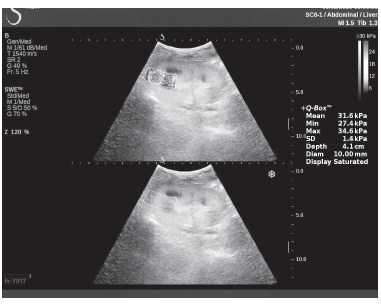

Клинический пример из второй группы. Пациент К. перенес операцию пересадки почки от живого родственного донора. Трансплантат в левой подвздошной области. Индекс резистентности в междольковых артериях составил 0,70 (рис. 5). В сегментарных артериях индекс резистентности составил 0,66 (рис. 6). Показатели жесткости паренхимы почечного трансплантата при режиме УЭСВ составили от 31,6 до 36,9 кПа (рис. 7-9).

Рисунок 9. Исследование в режиме ультразвуковой эластографии сдвиговой волны у пациента К.: жесткость паренхимы у верхнего полюса почечного трансплантата 31,6 кПа

При снижении скорости кровотока и повышении индекса резистентности до 0,70 и более, как в первой, так и во второй группах, показатели УЭСВ составили от 28,00 до 39,45 кПа. Повышение жесткости паренхимы почечного трансплантата, на наш взгляд, связано с начавшимися изменениями (фиброза) в паренхиме почки. При повышении индекса резистентности более 0,70 показатели жесткости паренхимы при УЭСВ является дополнительным критерием, позволяющим оценить функциональное состояние почечного трансплантата. Ультразвуковая эластография ― новая развивающаяся методика, чувствительность, специфичность и точность которой увеличиваются при комплексном использовании с другими методами исследования. Анализ результатов проведенных исследований выявил значительные клинические возможности и перспективы применения метода ультразвуковой эластографии сдвиговой волны в оценке состояния почечного трансплантата. Полученные данные о диагностической точности метода позволяют использовать результаты в целях принятия решения о дальнейшем ведении пациента и тактике лечения [4].